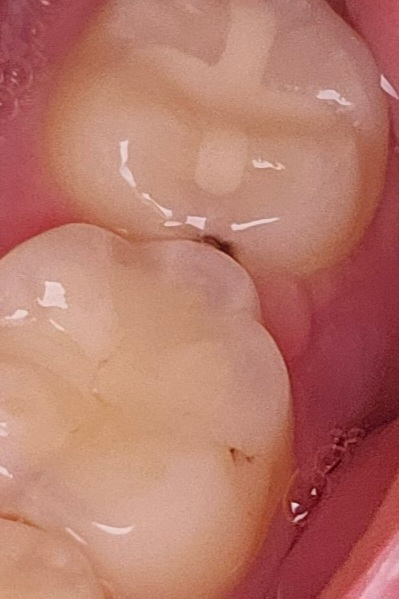

현재 인접면 충치가 제법진행이 된 것으로 보이며, 치아옆의 갈색도 충치가 진행되고 있는 것으로 보입니다. 따라서 가능한 빠른시일내에 치과에 방문하여 치료를 받길 권합니다.

눈에 보일정도가 저정도면 충치가 꽤 진행된 상태인거 같습니다. 엑스레이 사진을 찍어보고 치료를 하시는게 좋을것같습니다.

인접면 충치가 많이 진행된 편입니다. 간단하게 치료가 될 지는 치과에서 방사선 사진 등 검사해보셔야겠습니다.

1. 인접면 충치의 경우 정지우식이 되는 경우도 있으나 다소 진행이 빠른 경우도 있습니다. 시기가 다른 두 방사선 사진이 있다면 충치가 진행되고 있는지 확인할 수 있습니다. 만약 시간이 지나도 큰 변화는 없다면 그냥 두고 관리만 잘해주는 것도 나쁘지 않습니다. 현재 상태에서 저 인접면 충치를 치료하고자 한다면 딱 옆면만 치료하긴 어렵기 때문에 위에서부터 (씹는면에서부터) 뚫고 내려와야 합니다.

2. 옆 치아의 검은색은 수복재료 또는 치아의 변색으로 보입니다